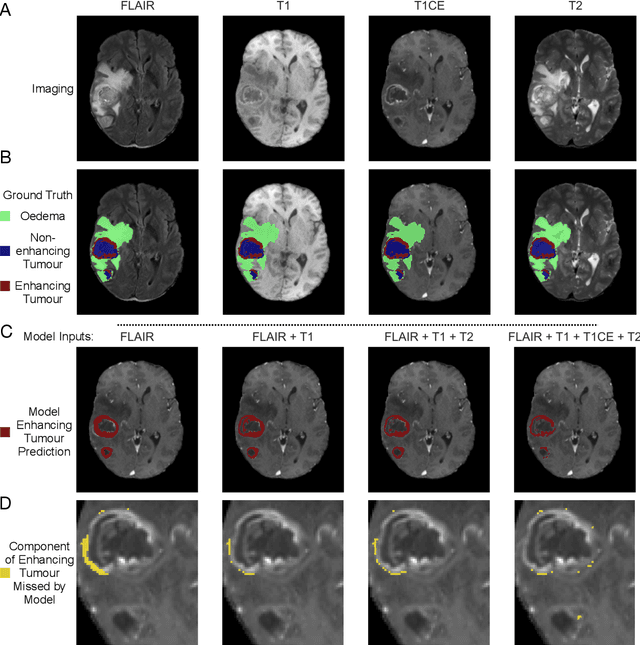

Abstract:Background: The complex heterogeneity of brain tumours is increasingly recognized to demand data of magnitudes and richness only fully-inclusive, large-scale collections drawn from routine clinical care could plausibly offer. This is a task contemporary machine learning could facilitate, especially in neuroimaging, but its ability to deal with incomplete data common in real world clinical practice remains unknown. Here we apply state-of-the-art methods to large scale, multi-site MRI data to quantify the comparative fidelity of automated tumour segmentation models replicating the various levels of completeness observed in clinical reality. Methods: We compare deep learning (nnU-Net-derived) tumour segmentation models with all possible combinations of T1, contrast-enhanced T1, T2, and FLAIR imaging sequences, trained and validated with five-fold cross-validation on the 2021 BraTS-RSNA glioma population of 1251 patients, and tested on a diverse, real-world 50 patient sample. Results: Models trained on incomplete data segmented lesions well, often equivalently to those trained on complete data, exhibiting Dice coefficients of 0.907 (single sequence) to 0.945 (full datasets) for whole tumours, and 0.701 (single sequence) to 0.891 (full datasets) for component tissue types. Incomplete data segmentation models could accurately detect enhancing tumour in the absence of contrast imaging, quantifying its volume with an R2 between 0.95-0.97. Conclusions: Deep learning segmentation models characterize tumours well when missing data and can even detect enhancing tissue without the use of contrast. This suggests translation to clinical practice, where incomplete data is common, may be easier than hitherto believed, and may be of value in reducing dependence on contrast use.